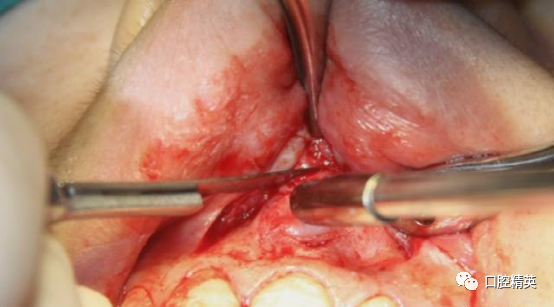

囊肿后壁与骨面粘连严重,术中破裂,可见大量豆渣样组织和药物颗粒。

初步清除。21根尖完全暴露。刮除21根尖区腭侧囊壁,此区域操作不便,易留有残留组织。